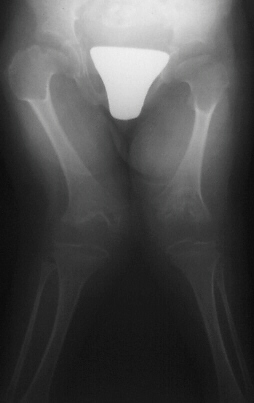

Hip dislocation and hip dysplasia have been reported, respectively

in 22% and 70% of patients. Delayed femoral head appearing, coxa valga

or, on the contrary, coxa vara are common findings.

- Long bones: they are broad and short. Metaphyses are flared and expanded.

A chevron-like shape is often present in femoral and tibial metaphyses.

Epiphyseal centers appear late and are severely irregular and flat. Ulna

and fibula are usually short.

Progressive genu valgum and increased flexion contractures of knees

and hips are now compromising the walking ability of the patient.

MRI C-spine. Hip arthrograms. Extension osteotomies for hip and knees.